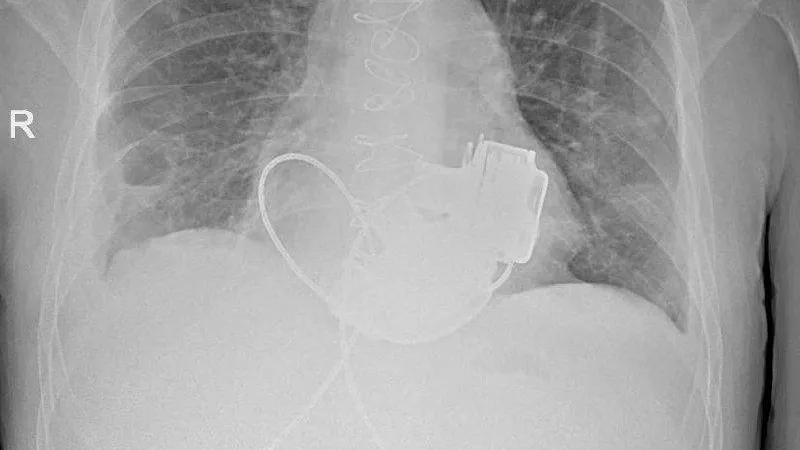

Пациент, которому впервые в России имплантировали сразу два искусственных желудочка сердца, готовится к выписке из Мариинской больницы в Санкт-Петербурге. Об этом сообщили в телеграм-канале городского комитета по здравоохранению.

Мужчина в возрасте 36 лет поступил в стационар с тяжелыми диагнозами: терминальной сердечной недостаточностью и кардиомиопатией. Медики заявили, что показатели работы сердца пациента были такими, будто он «уже не жив, а мертв».

«В Мариинской больнице готовится к выписке уникальный пациент, который с недавних пор живет без пульса», — заявили в комитете.

Операция по имплантации искусственных желудочков сердца была крайне сложной, но специалисты успешно справились с задачей. Процедуру провели под руководством главного внештатного специалиста по сердечно-сосудистой хирургии комитета по здравоохранению Санкт-Петербурга, академика РАН Геннадия Хубулавы.